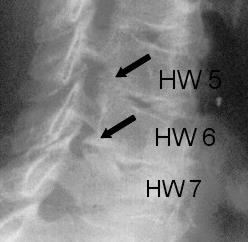

Der Eingriff wird in Vollnarkose und Bauchlagerung mit Überstreckung von Kopf- und Halswirbelsäule durchgeführt. Nach sorgfältigem Ablösen der sehr kräftigen Nackenmuskulatur von den hinteren Anteilen der Halswirbelsäule wird unter Röntgenkontrolle die richtige Etage verifiziert. Anschließend werden von hinten mit Mikrofräsen und Stanzen die aneinander grenzenden seitlichen Anteile der Wirbelhalbbögen entfernt. Der geschaffene, knöcherne Defekt ist in aller Regel kleiner als ein Fingernagel und verhilft dem Patienten zur Beschwerdefreiheit.